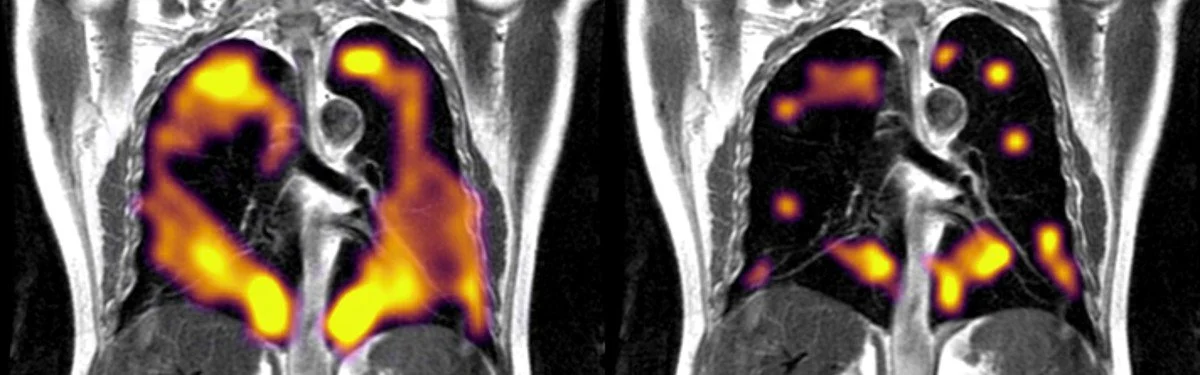

İngiltere’de yapılan kapsamlı bir pilot çalışması sonucunda koronavirüsü hafif atlatanların akciğerlerinde daha önce tespit edilemeyen bir hasar oluştuğu ortaya çıktı. Ülkenin saygın kurumlarından Oxford Üniversitesi, Sheffield Üniversitesi, Cardiff Üniversitesi ve Manchester Üniversitesi’nde görevli bilim insanlarının gerçekleştirdiği araştırmada, Covid-19’u hafif geçiren kişilerin uzun dönemde yaşadığı ve “Uzun Covid” olarak da bilinen sendromu incelendi. Bilim insanları, sağlıklı bir bireyin akciğer sonuçları ile (soldaki), Covid-19’u atlatan bir bireyin akciğer sonuçlarını karşı karşıya getirdi.

Bilim insanları, sağlıklı bir bireyin akciğer sonuçları ile (soldaki), Covid-19’u atlatan bir bireyin akciğer sonuçlarını karşı karşıya getirdi.KAN DOLAŞIMINA GİRMESİ ZAYIF

Bilim insanları koronavirüsü atlatsa bile halsizlik, nefes darlığı ve hatta konsantrasyon kaybı gibi sorunlar yaşayan insanların verilerini inceledi ve MR, röntgen sonuçlarını mercek altına aldı. Koronavirüsü hastaneye yatacak kadar ağır geçirmeyen kişilerin akciğerlerini inceleyen uzmanlar, Xenon gazı kullanarak tarama yaptı ve akciğerde daha önce tespit edilmeyen hasarın meydana geldiğini aktardı. MR sonucunda oksijen gibi hareket eden fakat taramada hareketleri takip edilebilen Xenon gazının kan dolaşımına nasıl dahil olduğu da yakından incelendi. Araştırma sonucunda bu gazın kana dolaşımında bir sıkıntı tespit eden uzmanlar, “Uzun Covid-19 sendromundan muzdarip kişilerde gaz transferi daha etkisiz” açıklamasını yaptı.SEBEBİNİ ARAŞTIRIYORLAR

Bilim insanları, sağlıklı bir bireyin akciğer sonuçları ile (soldaki), Covid-19’u atlatan bir bireyin akciğer sonuçlarını karşı karşıya getirdi.KAN DOLAŞIMINA GİRMESİ ZAYIF

Bilim insanları koronavirüsü atlatsa bile halsizlik, nefes darlığı ve hatta konsantrasyon kaybı gibi sorunlar yaşayan insanların verilerini inceledi ve MR, röntgen sonuçlarını mercek altına aldı. Koronavirüsü hastaneye yatacak kadar ağır geçirmeyen kişilerin akciğerlerini inceleyen uzmanlar, Xenon gazı kullanarak tarama yaptı ve akciğerde daha önce tespit edilmeyen hasarın meydana geldiğini aktardı. MR sonucunda oksijen gibi hareket eden fakat taramada hareketleri takip edilebilen Xenon gazının kan dolaşımına nasıl dahil olduğu da yakından incelendi. Araştırma sonucunda bu gazın kana dolaşımında bir sıkıntı tespit eden uzmanlar, “Uzun Covid-19 sendromundan muzdarip kişilerde gaz transferi daha etkisiz” açıklamasını yaptı.SEBEBİNİ ARAŞTIRIYORLAR